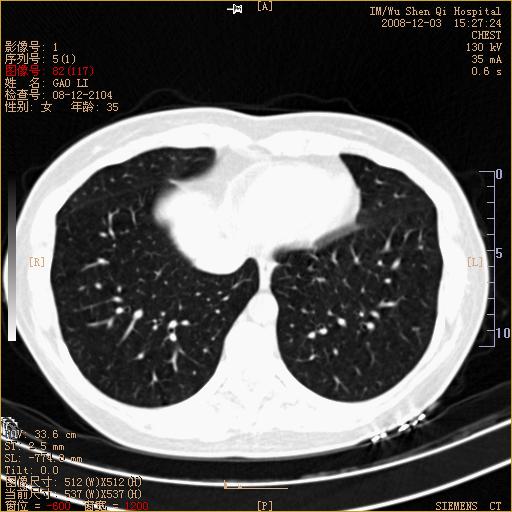

标题: CT16895:女,35岁,反复咳嗽数月,只传部分图像,是否考虑 [打印本页]

标题: CT16895:女,35岁,反复咳嗽数月,只传部分图像,是否考虑

左下肺支扩

典型“印戒征”。

印戒征,支持支扩.

左下肺扩支

印戒征,支扩